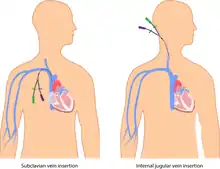

A central venous catheter (CVC), also known as a central line (c-line), central venous line, or central venous access catheter, is a catheter placed into a large vein. It is a form of venous access. Placement of larger catheters in more centrally located veins is often needed in critically ill patients, or in those requiring prolonged intravenous therapies, for more reliable vascular access. These catheters are commonly placed in veins in the neck (internal jugular vein), chest (subclavian vein or axillary vein), groin (femoral vein), or through veins in the arms (also known as a PICC line, or peripherally inserted central catheters).

Percutaneous central venous catheter (CVC)

A percutaneous central venous catheter, or CVC, is inserted directly through the skin. The internal or external jugular, subclavian, or femoral vein is used. It is most commonly used in critically ill patients. The CVC can be used for days to weeks, and the patient must remain in the hospital. It is usually held in place with sutures or a manufactured securement device.[28] Commonly used catheters include Quinton catheters.

Subcutaneous or tunneled central venous catheter

Tunneled catheters are passed under the skin from the insertion site to a separate exit site. The catheter and its attachments emerge from underneath the skin. The exit site is typically located in the chest, making the access ports less visible than catheters that protrude directly from the neck. Passing the catheter under the skin helps to prevent infection and provides stability. Insertion is a surgical procedure, in which the catheter is tunneled subcutaneously under the skin in the chest area before it enters the SVC. Commonly used tunneled catheters include Hickman, and Groshong, or Broviac catheters and may be referred to by these names as well.